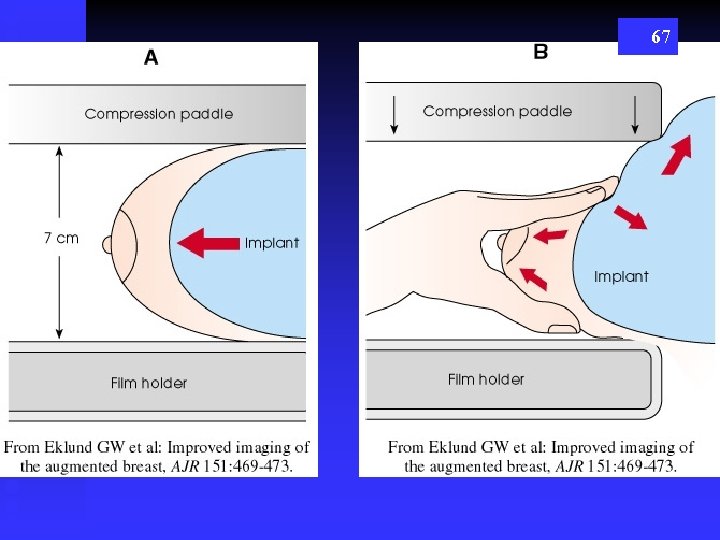

Elkland Method for Imaging with Breast Implants 66

67